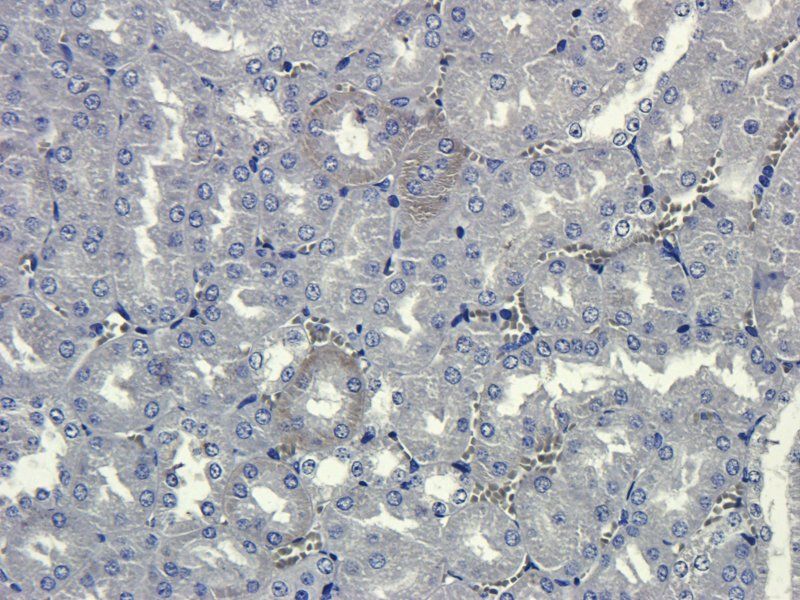

10 μg, 100 μg - Cubilin antibody [orb4997]Featured

ICC, IF, IHC-P, WB

Human, Mouse, Porcine, Rat

Rabbit

Polyclonal

Unconjugated

100 μg - PGP9.5 antibody [orb6713]Featured